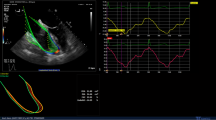

The midesophageal four-chamber view centred on the RV and the midesophageal RV inflow-outflow view were obtained. Imaging of eight consecutive beats was digitally recorded for later analysis. The sector width and depth were adjusted to achieve a frame rate of approximately 50-60 Hz. The transgastric RV inflow view was obtained and modified to align tricuspid annular motion with the Doppler plane at the edge of the two-dimensional (2D) sector by advancing the probe further into the stomach and adjusting the multiplane angle to approximately 130-160°. A colour tissue Doppler sector was applied to the tricuspid annular region where sector width and depth were adjusted to obtain a colour tissue Doppler frame rate of at least 200 Hz, as described previously14 (Fig. 1). Eight consecutive beats were digitally recorded for later analysis. The same observer used a GE workstation to analyze all echocardiographic images offline.

Colour tissue Doppler IVA

In the modified transgastric RV inflow view, a 6 × 6 mm sample volume was applied to the tricuspid annulus in the colour tissue Doppler sector, as previously described.15 Using quantitative analysis software (GE, Milwaukee, WI, USA), the IVA was measured as the gradient of the annular velocity during the pre-ejection phase and expressed in m·sec−2. Measurements were averaged over five normally conducted beats (Fig. 1).